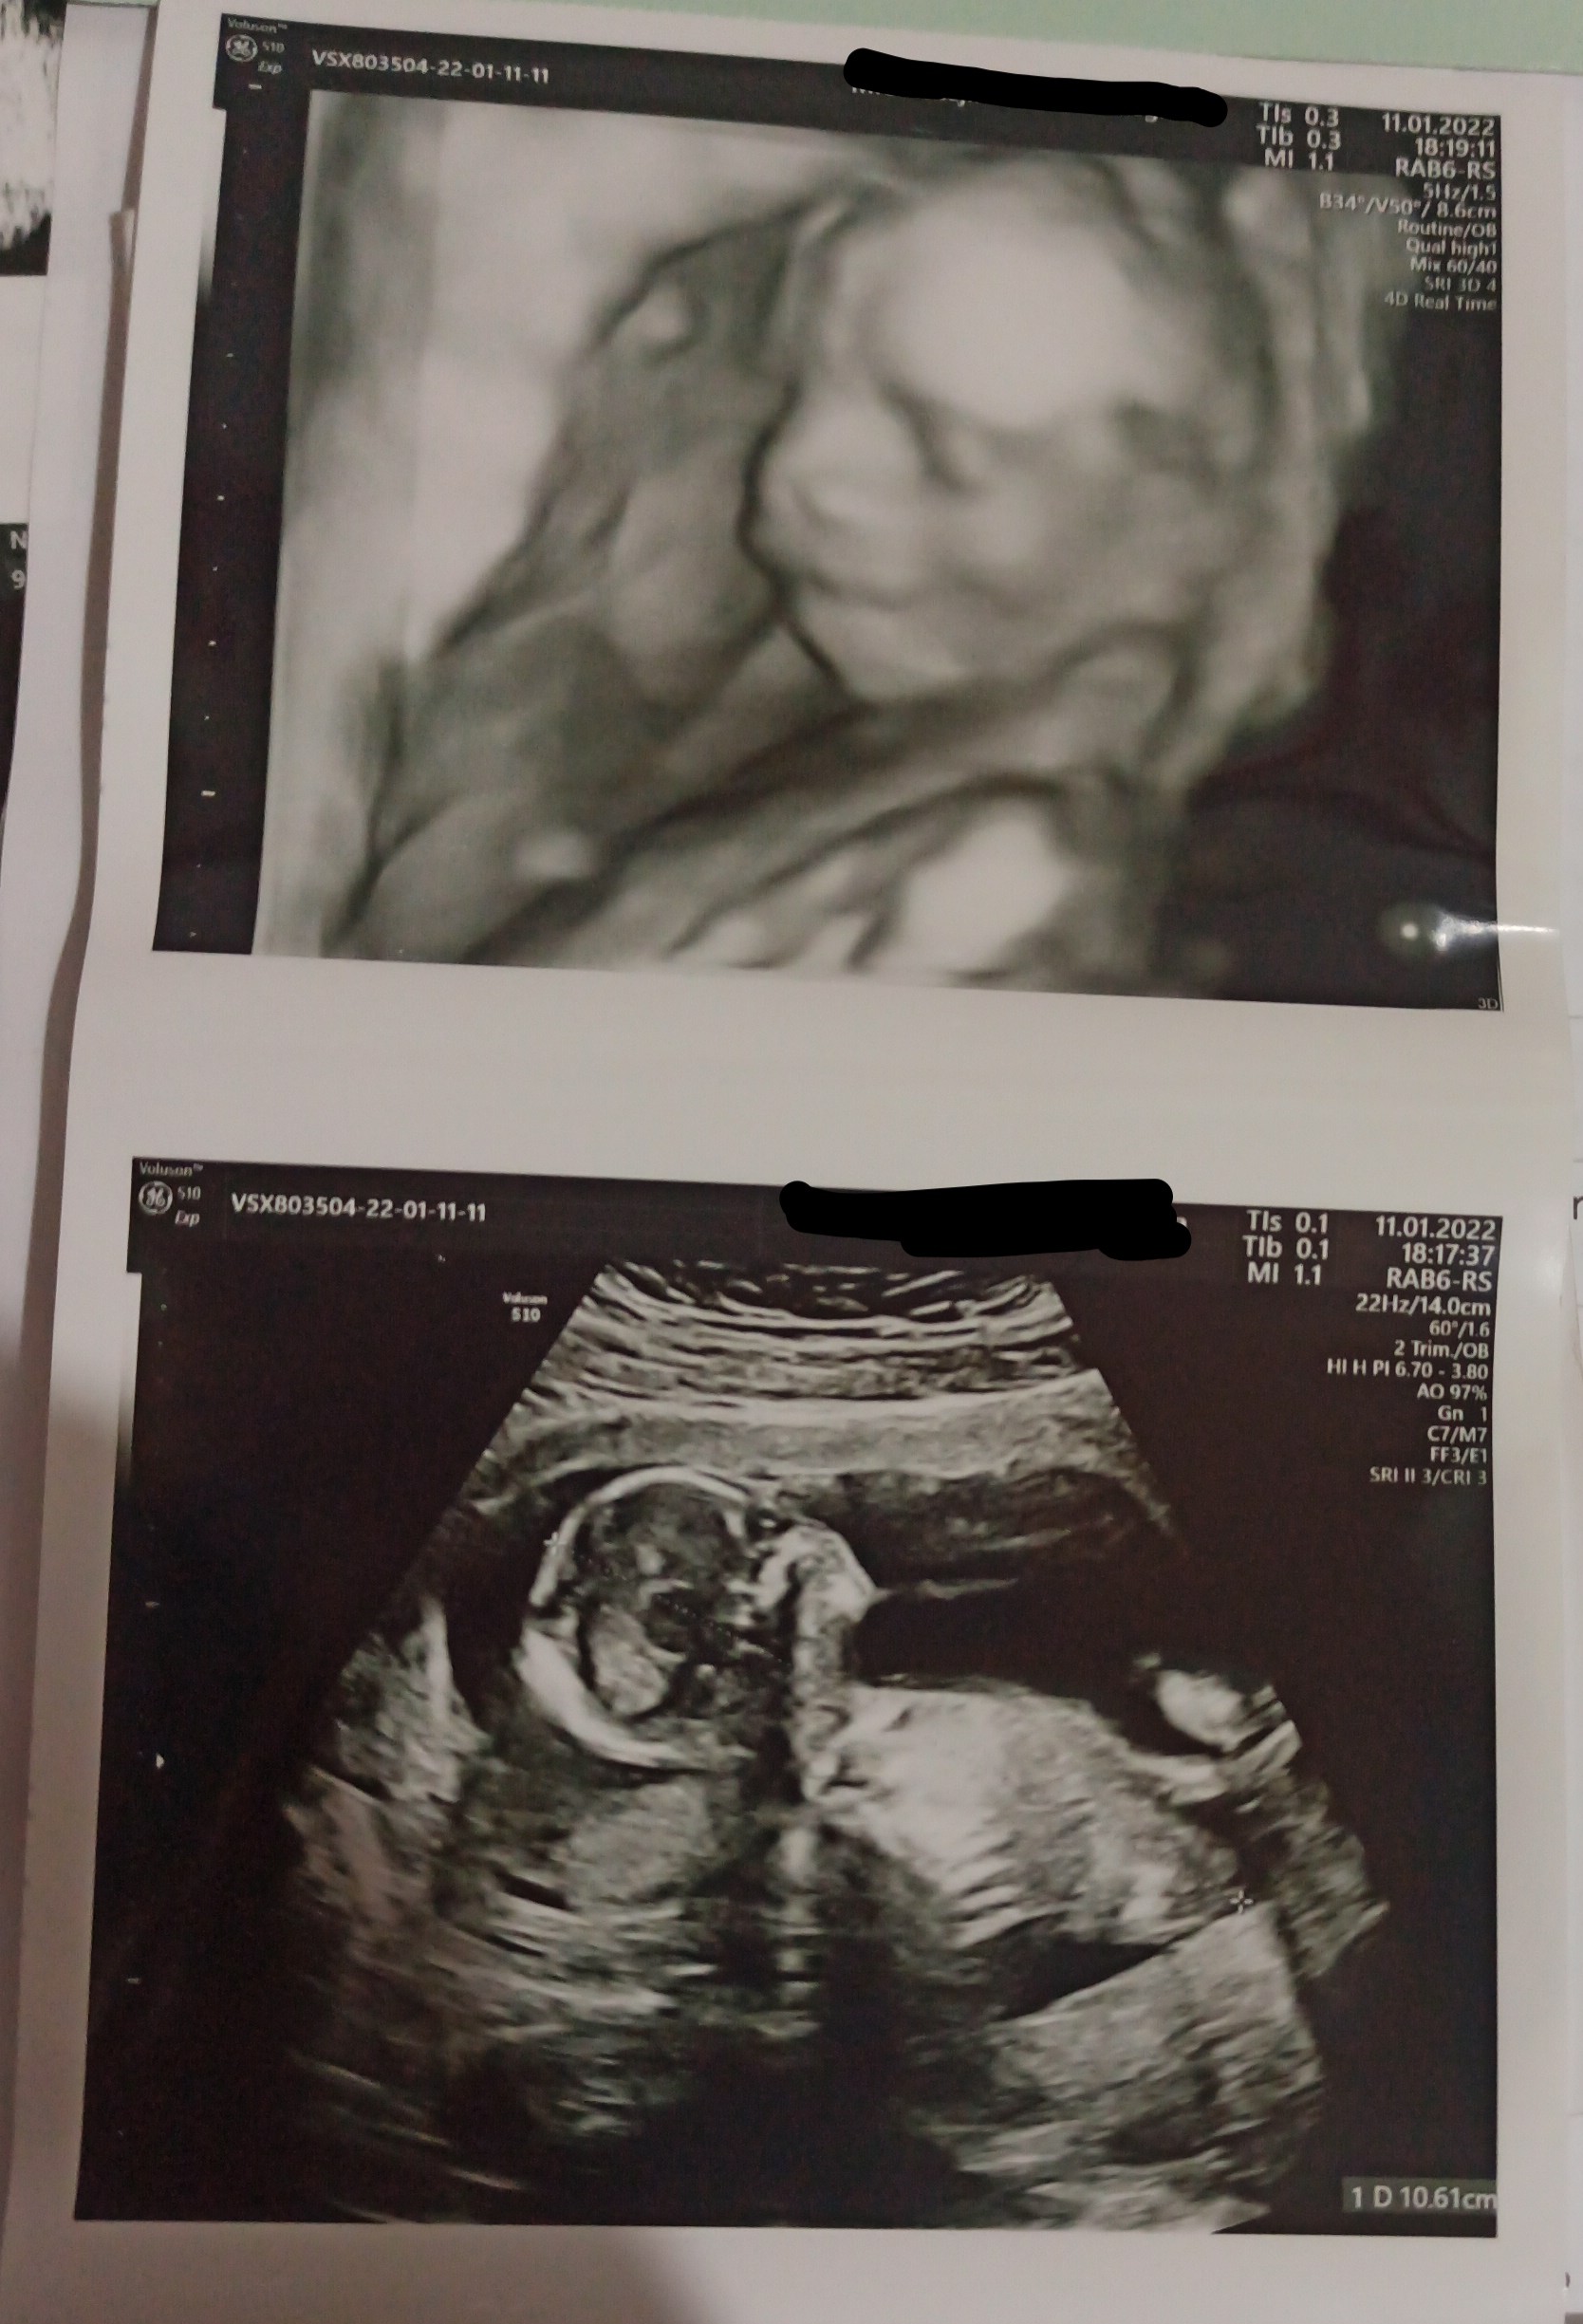

A ja dziś zaczęłam 16+0, jestem po wizycie u mojej gin i odpukać, ale chyba jest wszystko dobrze.. Moja lekarz każe mi odetchnąć z ulgą, bo badanie jest w porządku, dzidzia się wierci, rośnie, serduszko i narządy ok. Z badań krwi, kontrolnych nie ma tragedii, jedynie tsh mi mocno skoczyło i mam 3,100 mniej więcej, ale dostałam od niej leki i jestem dobrej myśli. Załączę USG, bo po raz pierwszy dostałam i widziałam moje dziecko w 3D.. Mam nadzieję, że niedługo też będę mogła zobaczyć wasze maluchy. Chciałabym się zacząć cieszyć i wyluzować, ale powtarzam sobie co wizytę, że jak będzie w porządku to już się uspokoję i średnio mi to idzie. Za miesiąc połówkowe, może wtedy...

Dalej prawdopodobnie dziewczynka.